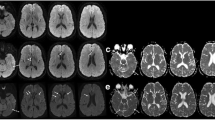

The presence of Aβ pathology was searched for in all of the 27 iCJD and 67 sCJD cases. Cases were considered positive when at least one Aβ CP containing amyloid (Thioflavin S or Congo red positive) and/or one blood vessel harboring Aβ deposits consistent with CAA were identified in at least one histology section of a minimum of two (Table 1, Fig. 3 and Materials and Methods). Eleven of 21 iCJD cases (52%) fulfilled these selection criteria. They comprised three of the eight cases of GH-iCJD, eight of the 13 cases of DM-iCJD including the two cases of iCJDMMi (cases 9 and 21 of Table 1, Fig. 4 and Additional file 2: Table S4). Despite the relatively small size of the Aβ-positive iCJD subset, a trend could be detected when basic clinical and molecular features as well as the histopathological phenotypes were comparatively analyzed in Aβ-affected and -unaffected groups and their subsets. Subjects harboring Aβ pathology were older in each iCJD subset. Age differentials varied from ~14 to 17 years, while the incubation period was ~13 years longer in Aβ-positive GH-iCJD cases (Fig. 5). Regarding the 129 genotype, the prevalence of the MV and VV genotypes over the MM genotype observed in all iCJD cohort was slightly increased in Aβ-positive iCJD cases (57% vs. 66%) (P > 0.05) (Figs. 1 and 5). Furthermore, histopathological phenotypes were similarly distributed in the two iCJD groups. In Aβ-positive iCJD cases (8, 9, 10 and 27 of Table 1) with available frozen tissue the Illumina and Sanger sequencing of APP, PSEN1, and PSEN2 genes identified no novel rare variants nor known mutations. Furthermore, ApoE genotyping available in Aβ-positive iCJD (8, 9, 10 and 27 of Table 1) and sCJD (65, 66 and 67 of Additional file 1: Table S2) cases underlined the lack of ApoE-ε4/4, and the presence of ApoE-ε3/3 in all CJD cases with the exception of one iCJD (case 8) that had genotype ApoE-ε2/3.

Aβ and tau pathology of iCJD, sCJD and AD. a and b typical Aβ CP (arrows) from the frontal cortex of iCJD (a) and AD (b); inset a: Aβ CP at higher magnification immunoprobed for Aβ (top) or stained with Thioflavin S (bottom); inset b: Thioflavin S-positive Aβ CP. c diffuse plaques from the frontal cortex of a case of sCJD; inset: Thioflavin S-negative staining of plaques (dashed rectangle). d co-localization of Aβ (cyan dye) and PrP (brown dye) immunoreactivity in the same plaque from cerebral (I and III) and cerebellar (II) cortices of iCJD. I: plaque exhibiting a PrP-positive core surrounded by an Aβ immunoreactive crown; II-III: plaques showing either the immunostaining opposite to that of I, with Aβ-positive core and a PrP immunoreactive crown (II), or random distribution of PrP- and Aβ-reactive aggregates (III). e-g Aβ deposits (e) and Thioflavin S-positive staining (f and g) of vessels in frontal cortex (e), hippocampus (f) and cerebellum (g) in iCJD; f: DG, Dentate gyrus; g: asterisk, Aβ CAA in the subarachnoid space between two cerebellar folia. h Aβ CP predominantly affecting the granular layer (Grl. L) and Purkinje layer of the cerebellum in iCJD (case 9, Table 1); arrow indicates Aβ CP; large and small insets: enlargements of Aβ CP identified by the dashed rectangle in the main figure and a Thioflavin S-positive Aβ CP, respectively. i-j hippocampus free of tau pathology in iCJD (i) but severely affected in AD (j). k Tau-positive DN associated with an Aβ CP in frontal cortex of iCJD (case 8, Table 1) (dashed square); top inset: enlargement of tau reactive DN identified in dashed square; bottom inset: DN associated with a PrP kuru plaque in iCJD (occipital cortex, case 9, Table 1). l globose NFT (arrow) and neuropil threads (arrowhead) in the nucleus basalis of Meynert of iCJD (case 6, Table 1); inset: flame-shaped NFT in the temporal neocortex of the same iCJD case. Abs: 3F4 (d), 4G8 (a-e, h) and AT8 (i-l) to PrP, Aβ and phosphorylated tau, respectively; Thioflavin S to Aβ (a-c, f-h)

Aβ phenotype and age distribution in Aβ-positive iCJD and control cases. a: iCJD (N = 11); b: sCJD (N = 9); c: non-ND (N = 2). Scores for the Aβ phenotype is relative to the presence of either Aβ CP or CAA (score 1), or combinations of both (score 2). Brackets below dotted line in the X-axis underline cases of the same age; GH: growth hormone; DM: dura mater